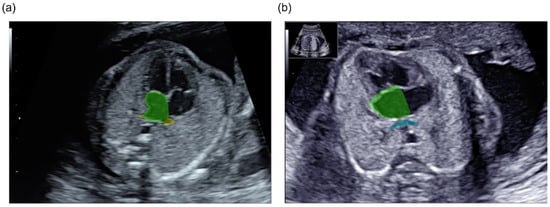

Total anomalous pulmonary venous connection (TAPVC) is one of the most severe congenital heart defects; however, prenatal diagnosis remains suboptimal. A normal fetal heart has a junction between the pulmonary venous (PV) and left atrium (LA). In contrast, no junctions are observed in [...] Read more.

Total anomalous pulmonary venous connection (TAPVC) is one of the most severe congenital heart defects; however, prenatal diagnosis remains suboptimal. A normal fetal heart has a junction between the pulmonary venous (PV) and left atrium (LA). In contrast, no junctions are observed in patients with TAPVC. In the present study, we attempted to visualize and detect fetal PV-LA connections using artificial intelligence (AI) trained on the fetal cardiac ultrasound videos of 100 normal cases and six TAPVC cases. The PV-LA aggregate area was segmented using the following three-dimensional (3D) segmentation models: SegResNet, Swin UNETR, MedNeXt, and SegFormer3D. The Dice coefficient and 95% Hausdorff distance were used to evaluate segmentation performance. The mean values of the shortest PV-LA distance (PLD) and major axis angle (PLA) in each video were calculated. These methods demonstrated sufficient performance in visualizing and detecting the PV-LA connection. In terms of TAPVC screening performance, MedNeXt-PLD and SegResNet-PLA achieved mean area under the receiver operating characteristic curve values of 0.844 and 0.840, respectively. Overall, this study shows that our approach can support unskilled examiners in capturing the PV-LA connection and has the potential to improve the prenatal detection rate of TAPVC. Full article

Figure 1